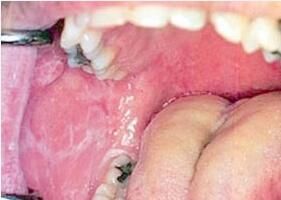

对于口腔扁平苔藓的发病原因,中医和西医各有不同的说法,我们去研究和挖掘导致口腔扁平苔藓的原因,也是为了能够进行很好的治疗工作。

口腔扁平苔藓病因解说

西医认为口腔扁平苔藓病因尚不明确,从临床和基础中发现可与病毒或细菌感染、遗传、慢性肝炎、胃溃疡等系统疾病,及*亢进等有关。看来其他疾病如果不及时治疗也可影响到口腔扁平苔藓的发作。

中医认为口腔扁平苔藓与“口破”、“口糜”相象,与“口蕈”、“口藓”类似。口腔扁平苔藓发病与内伤七情,外感风热燥邪有关。如思虑过度,损伤脾胃,脾失健运,水温内停,蕴而化热,热则生燥,燥胜则干,导致粘膜粗糙,白色条纹,渗出糜烂,外感风热,入里化火,上蒸于口,也可加重口腔扁平苔藓病情。因脾为后天之本,主一身肌肉,开窍于口,肝主疏泄,怒则伤肝,肝阳上亢,耗伤阴血,更增内燥,常责之于脾、肝两经。